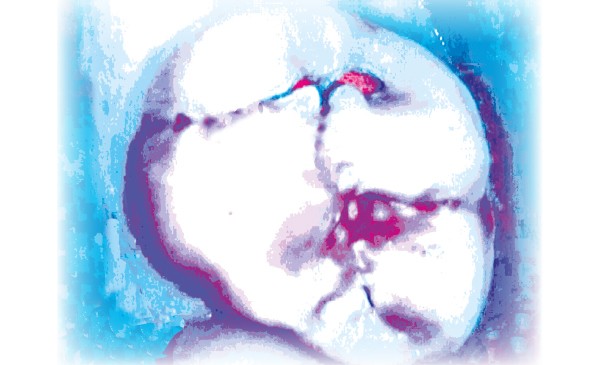

Les scellements préventifs et thérapeutiques font partie de l’éventail des procédures cliniques appliquées à l’intervention minimale qui est le concept de prise en charge globale du patient regroupant toutes les mesures préventives et thérapeutiques à mettre en œuvre pour enrayer l’apparition, la progression et la récidive des maladies affectant les tissus durs dentaires et le parodonte (préventions primaire, secondaire et tertiaire) [1]. Ils peuvent être mis en place à titre préventif [2], mais aussi thérapeutique dans le cas de lésions carieuses non cavitaires [3, 4]. Ils consistent, dans les deux cas, en un acte strictement non invasif visant à combler les puits et sillons des faces occlusales avec un matériau adhésif. Réalisés à titre préventif, ils constituent une barrière physique étanche qui s’oppose à l’accumulation de plaque et à la déminéralisation. Réalisés à titre thérapeutique dans le cas de lésions carieuses non cavitaires, la barrière physique permet l’arrêt du processus carieux en privant les bactéries cariogènes présentes dans la lésion de carbohydrates fermentescibles [5]. En France, la Haute Autorité de Santé (HAS) [6] a édicté, en 2005, des recommandations sur l’appréciation du risque carieux individuel (RCI) et les indications du scellement préventif des premières et deuxièmes molaires permanentes chez les sujets de moins de 18 ans. Elle recommande la pose de scellements préventifs chez les patients à RCI élevé et âgés de moins de 20 ans. Malheureusement, aucune recommandation, ni consensus n’existent en France concernant l’utilisation des scellements thérapeutiques. Il semble qu’il existe de grandes variations entre les recommandations en matière de scellements. Par exemple, aux États-Unis, Beauchamp et coll. et l’American Dental Association [7, 8] recommandent le placement de scellements préventifs lorsque le risque carieux est élevé à l’échelle individuelle ou…